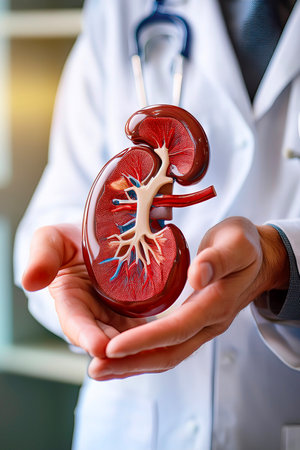

Detailed model of a human kidney held in a hand for educational purposes in a neutral setting

Model of human kidney held in a hand showcasing internal structure and details for educational purposes

Model of human kidney held by hand with colored features visible

Human Kidney Model with Chronic Kidney Disease Damage Held by Doctor